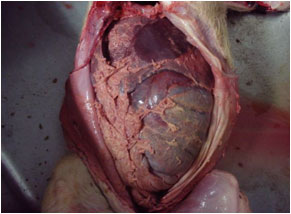

剖検:

- (1)肝の腫脹と小白色壊死斑の散在

- (2)脾腫

- (3)咽頭、膀胱粘膜の点状出血

- (4)腸管膜リンパ節の腫脹及び充出血